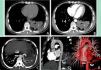

The most common lesions of pulmonary sequestration were mass lesions (n=16, 37.2%; Figure 1), followed by cystic lesions (n=14, 32.6%). The mass lesions had a maximum diameter of 1.7–9.8 cm. There was mild enhancement in most mass lesions and the solid parts of cavitary lesions, while no enhancement was observed in cystic lesions. The pathological results of one patient who had a cavitary lesion with a gas-fluid interface proved to be accompanied by a Mycobacterium tuberculosis infection (Figure 2). Three patients with mass lesions had obvious enhancement. Thirteen patients (30.2%) had lesions with calcification.

A 32-year-old male with intralobar sequestration. A and B: Axial multidetector computed tomography images show a mass in the right lower lobe (S); C: An axial multidetector computed tomography image obtained at a level lower than A and B shows an aberrant artery (curved arrow) arising from the thoracic aorta (straight arrow) to the sequestered lung (S); D: A 3D multidetector computed tomography volume rendering image shows an aberrant artery (curved arrow) from the thoracic aorta (straight arrow) to the right lower lobe.